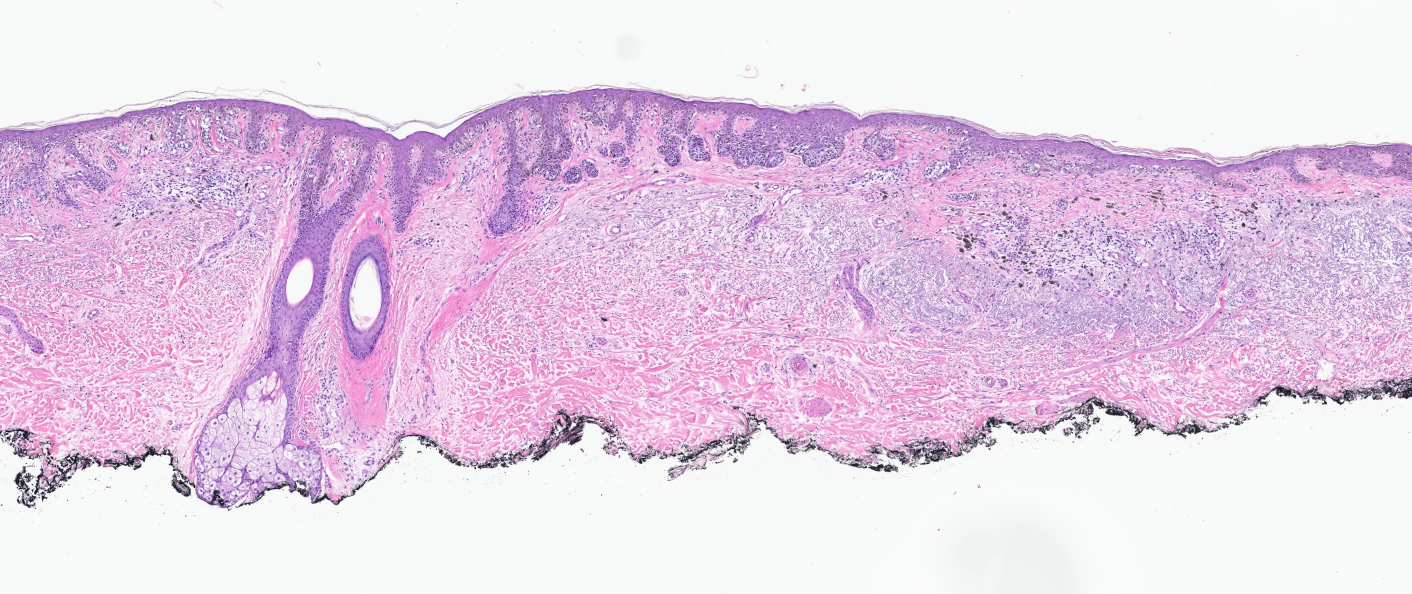

Microscopic (histologic) description

- Proliferation of intraepidermal (single and nested) melanocytes overlying solar elastosis

- Melanocytes demonstrate crowded growth along the basal epidermis

- Associated epidermal alterations, including loss (effacement) of epidermal rete and associated irregular epidermal hyperplasia

- Pagetoid scatter (melanocytes above the basal layer)

- Involvement of adnexal epithelium

- Melanocytic cytology is variable, ranging from small cells with dark nuclei and scant cytoplasm to epithelioid pigmented melanocytes, to spindled melanocytes

- Invasive component, if present, consists of single or nested melanocytes in the dermis with similar cytologic features to those in the in situ component (Cancer Res 1969;29:705, Am J Pathol 1969;55:39)

Microscopic (histologic) images

Contributed by Joseph Gillam, M.D., Jennifer Crimmins, M.D. and Mark Mochel, M.D.